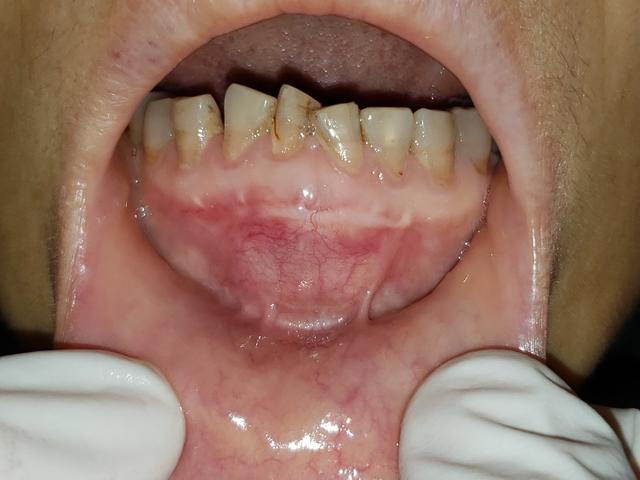

图一:患者图片

这个患者三个月前最先 下前牙区肿痛,临床体查见下前牙区局部膨隆。病理活检陈诉:切合牙源性囊肿。